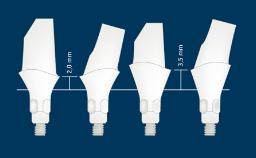

所有种植修复体的设计都应基于修复计划,并应满足所有相关的设计因素。大多数种植体固定义齿(或 FDP)的设计有许多共同点,以合理的设计遵循这些共同点很有帮助。第一要点是选择 FDP 的类型和方案。下一要点是选择固位方式,然后是考虑所需的外部和内部结构,以满足美观、功能和强度等因素。本模块将依次探讨每个设计要点。本网络学院设有单独且更详细的单元,将以现有模块为基础,阐述 FDP 修复材料、基台和种植体的选择。

- 外部设计

- 内部设计